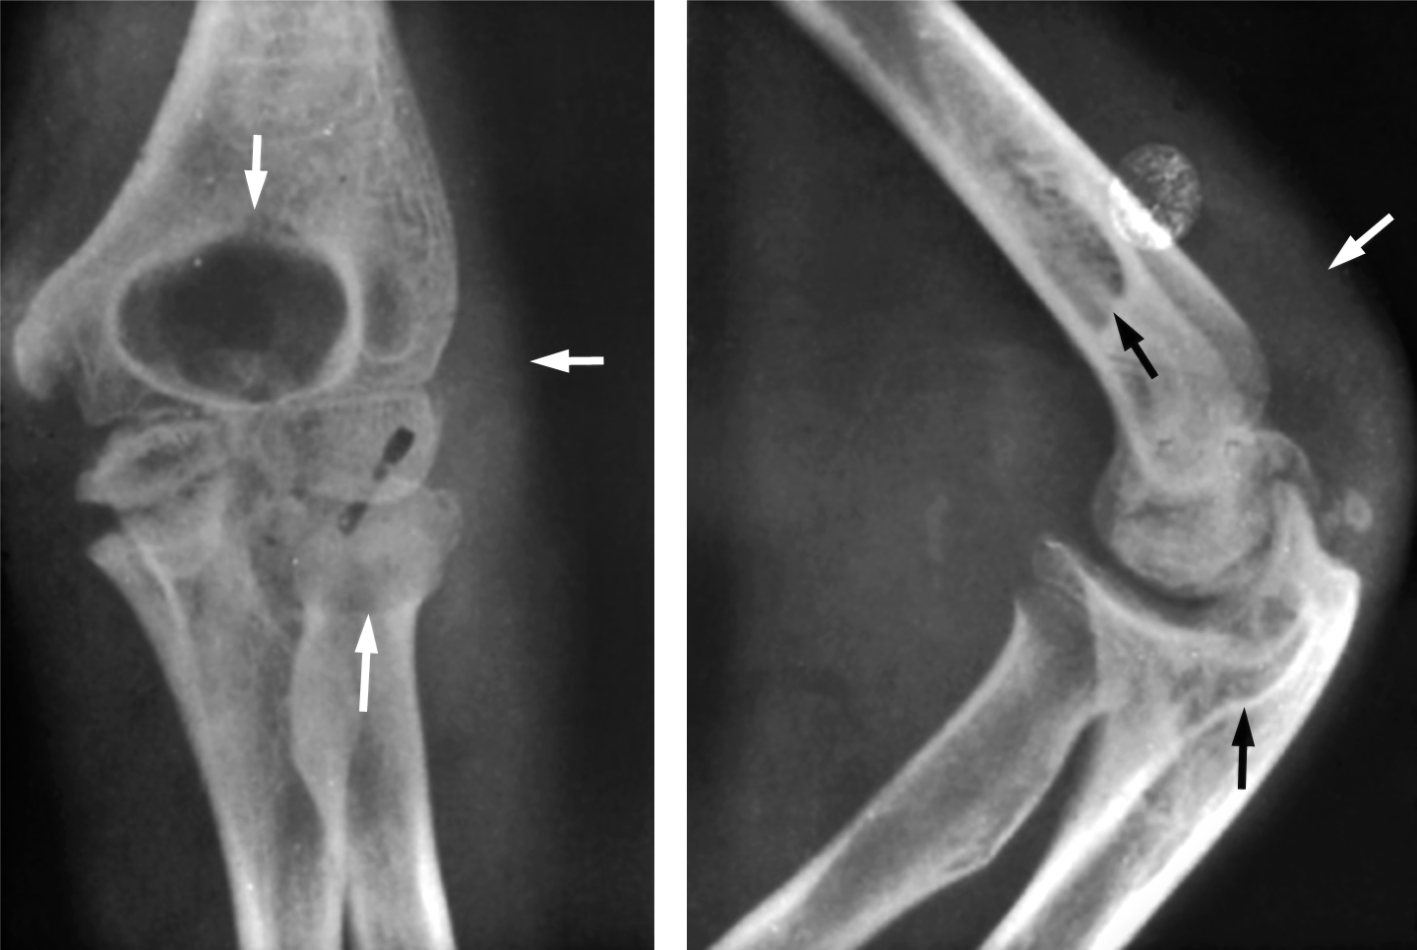

تصاب الرئتان بأنواع مختلفة من الأورام السليمة والخبيثة، بعضها أولي، وبعضها ثانوي انتقالي. تُعدّ السرطانة القصبية أكثر الأورام الرئوية شيوعاً (< 90%)، أما الأورام السليمة مثل الورم العابي hamartoma والورم الغدي في الغدد القصبية فنادرة